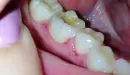

В последнее время, примерно 2 недели, очень сильно стали кровоточить дёсны при чистке зубов. Раньше такое наблюдалось, но не так сильно.

Вчера вечером появился дискомфорт при приёме пищи, было больно пережёвывать. Сегодня утром обнаружила язвы на дёснах. Не могу нормально есть и пить, болезненные и неприятные ощущения. Никаких других симптомов нет (повышенная температура и пр.). Несколько лет назад у меня был стоматит.

Это может быть стоматит? Что предпринять? Чем лечить?

К сожалению, без клинического осмотра и оценки лабораторных данных сложно судить о причине возникновения образований. Это может быть аллергическая реакция или инфекционное поражение. Вам необходимо обратиться к терапевту общего профиля для контроля состояния по лабораторных данным.